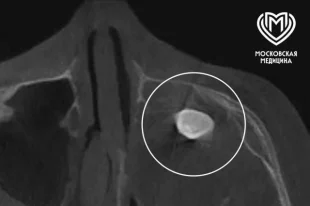

Почти трепанация. Хирург Голованёв открыл секреты операций на черепе

Как черепу возвращают форму хирургическим путем.